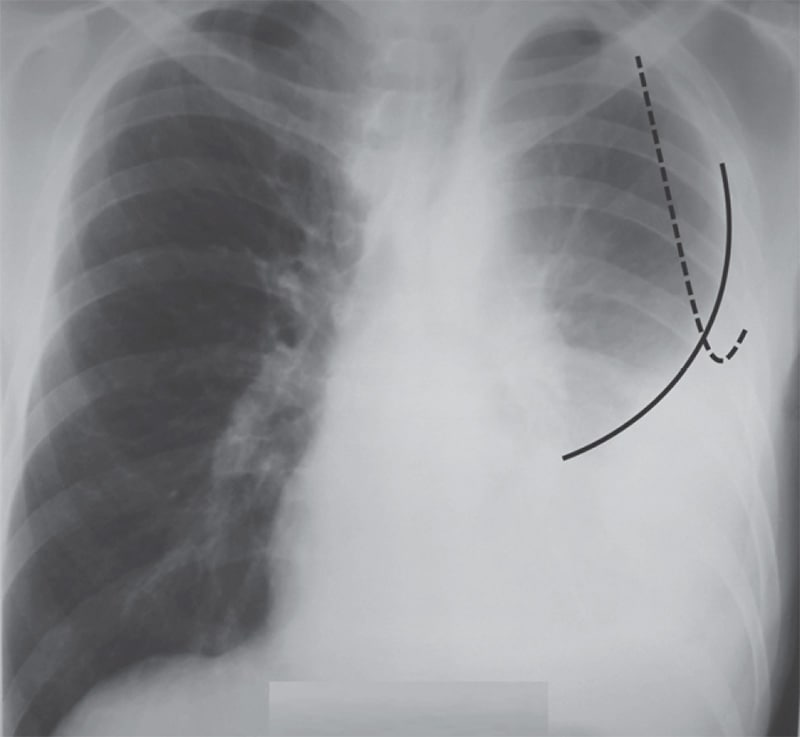

Симптомы и причины скопления воды в легких

Раздел: Ракурсы просвещения